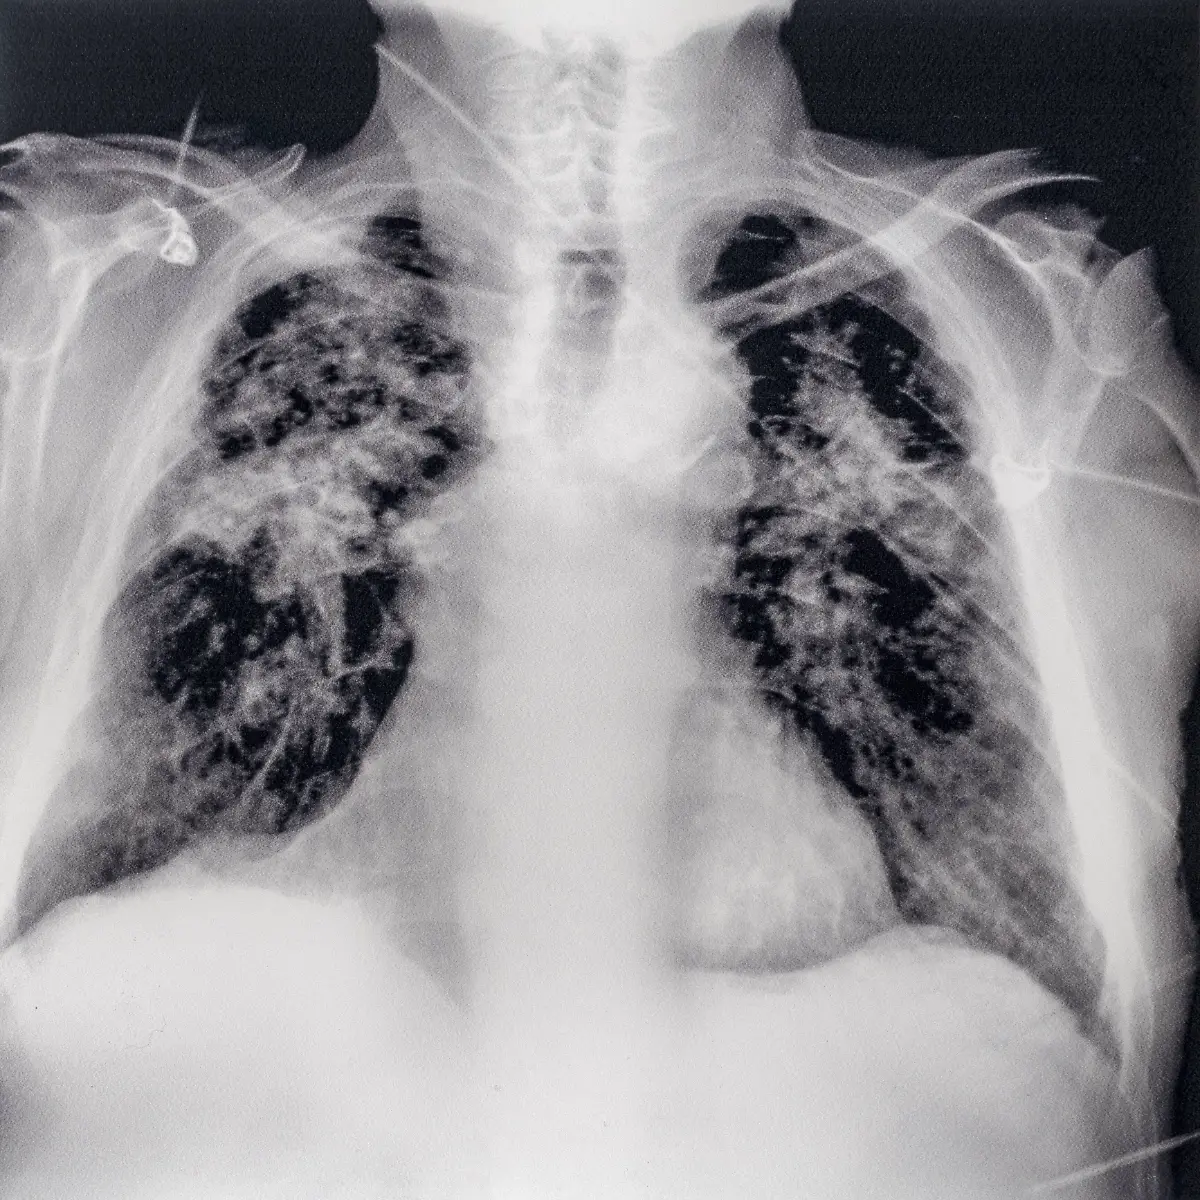

Er war ein Revolutionär der Medizintechnik: Der Physiker Wilhelm Conrad Röntgen entdeckte 1895 zufällig die X-Strahlen, was nicht nur für die Diagnostik in der Medizin ein Meilenstein war. Später wurden die Strahlen und das Verfahren nach ihm benannt. Röntgen starb vor 100 Jahren in München.